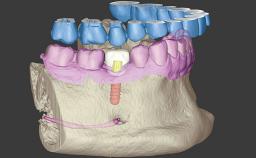

Replacing Four Upper Incisors with a Screw-Retained Bridge on Two Implants

A 22-year-old female patient was referred to our office for implant therapy following an accident in which the patient lost the upper left central incisor (tooth 21). The adjacent teeth had also been damaged; the right central incisor (11) and both lateral incisors (12, 22) showed grade II mobility. Immediately after the accident the first dental intervention involved repositioning of the mobile teeth and rigid splinting .